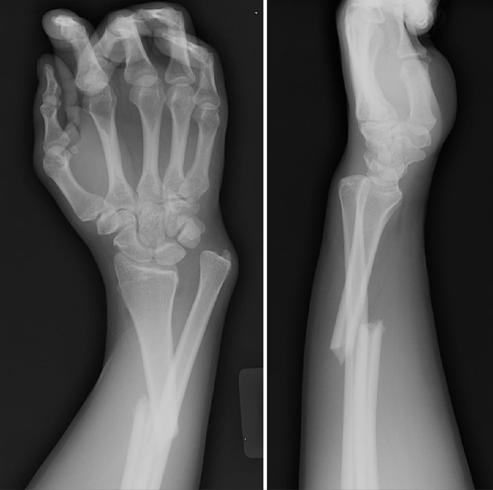

Pasienten har tatt seg for ved fall. Nå hevelse, smerte og feilstilling i underarm. Diagnose?

Antebrakiumfraktur.